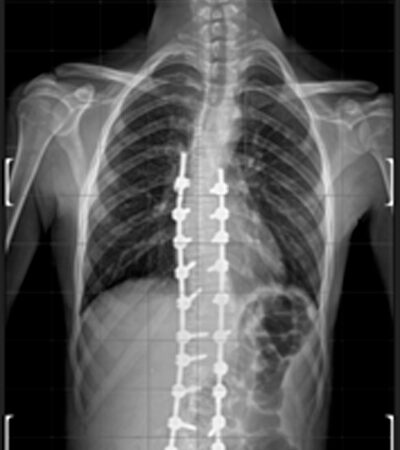

DIAGNOSI:

Scoliosi dorso lombare

Radiografia della colonna in toto pre-operatoria